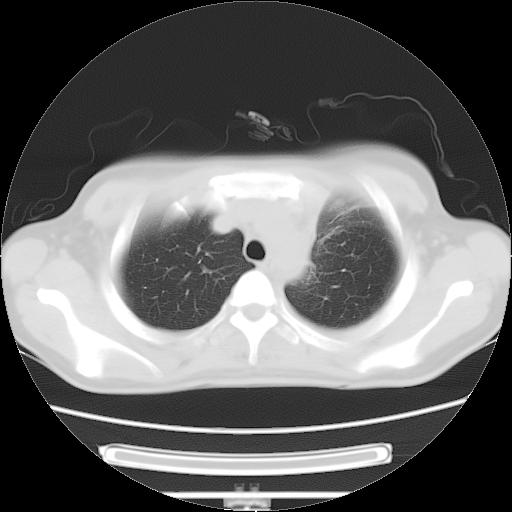

女,29岁,胸部不适,在外院胸片提示胸腔积液,到我院ct检查。

肺窗: